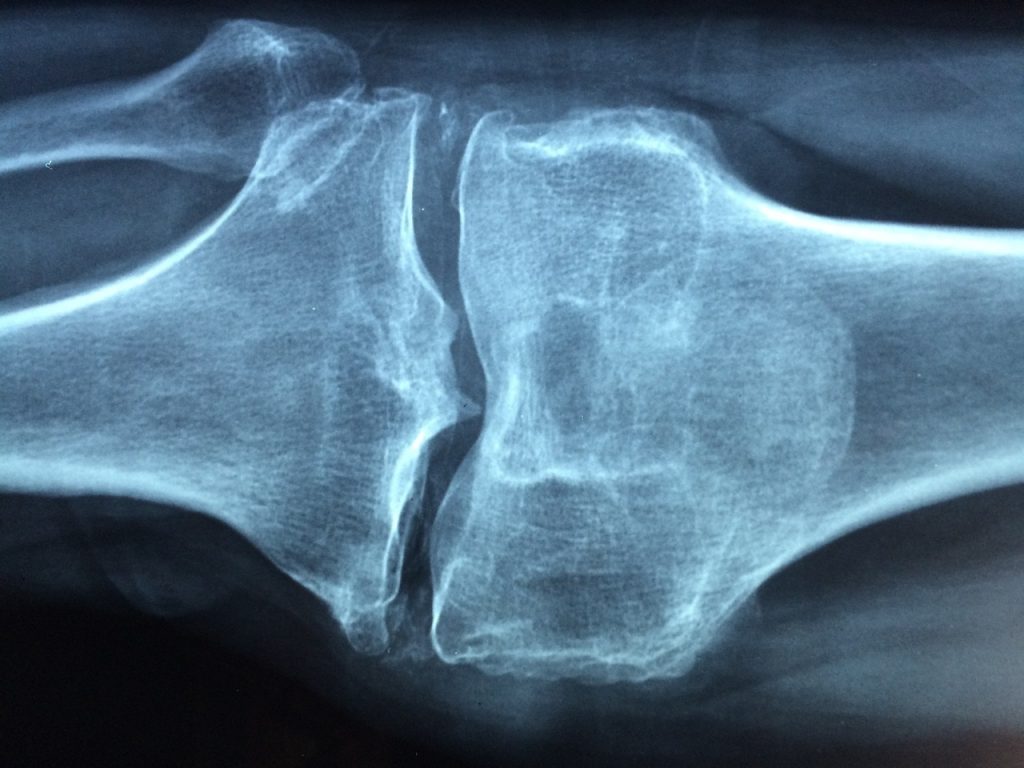

La densitometria ossea è un esame fondamentale per la diagnosi di osteoporosi o di altre pato...